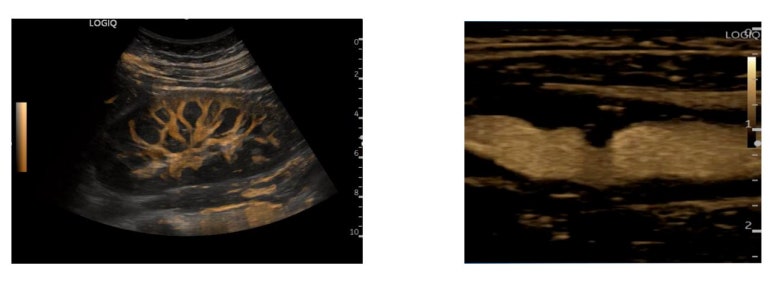

B-Flow

비플로우 옵션은 주로 경동맥이나 심혈관계 등 혈관을 검사하는 기능입니다.

특이하게 도플러 기능을 사용하지 않고 B모드상에서 강하게 돌아오는 조직의 신호는 제거하고 적혈구에서 돌아오는 약한 신호만 증폭시켜 혈류역학적인 영상을 만들어주는 GE의 고유 기술입니다.

도플러를 쓰지 않으니까 구불 구불하게 사행하는 혈관도 끊김없이 번지지 않게 표현해주고요.

혈관 위로 겹치는 아티팩트나 에일리어싱 현상이 없어 혈관벽의 정확한 경계를 보여줍니다.

임상적으로 고지혈증 및 동맥경화에 진단에 유용합니다.